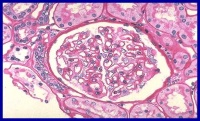

肝肾综合征(hepatorenal syndrome,HRS)是指在严重肝病时发生的功能性急性肾功能衰竭(functional acute renal failure,FARF),临床上病情呈进行性发展。HRS是一种严重肝病伴有的特异性的急性肾功能衰竭,其最大的特点是这种急性肾功能衰竭为功能性,一般认为此种FARF在病理学方面无急性肾小管坏死或其他明显的形态学异常。

多数无明显的形态学改变,部分并发胆汁肾病,肝性肾小球硬化偶见肾小管上皮细胞坏死。